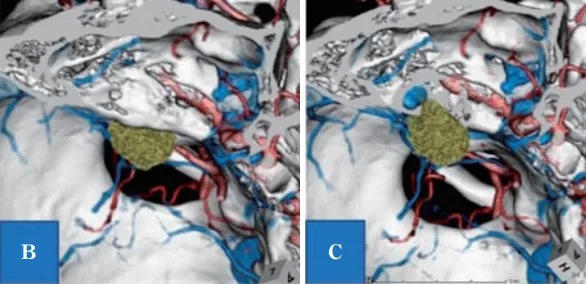

B:计算机断层扫描-骨骼血管造影(CTA)显示,左上前侧有肿瘤(绿色肿块是增强区域);C:B所示的IAC壁骨缺失,显示颈高球非常靠近内听道和肿瘤。